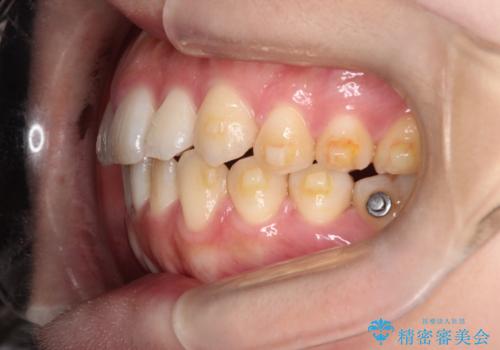

【インビザライン】前歯の凸凹を治したい

- 前歯の凸凹を主訴に来院されました。

インビザラインにて臼歯部の遠心移動を行いながら、できるだけ前歯が出ないように気を付けて治療を行っています。

遠心移動を行う必要があったので、患者様には顎間ゴムを使用していただきました。